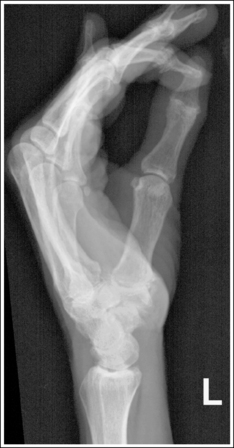

See Figures 4-16 and 4-17 and Box 4-6.

The thumb demonstrates a lateral projection. The anterior aspect of the proximal phalanx and metacarpal demonstrates midshaft concavity, and the posterior aspect of the proximal phalanx and metacarpal demonstrates slight convexity.

• To accomplish a lateral thumb projection, place the patient's hand flat against the IR; then flex the hand and fingers only until the thumb naturally rolls into a lateral projection (Figure 4-18). Overflexion causes superimposition of the second and third proximal metacarpals onto the proximal first metacarpal, obscuring it (see Image 14). When the hand and fingers are accurately flexed and the thumb is in a lateral projection, the midshaft of the proximal phalanx and metacarpal demonstrates concavity on their anterior aspects and convexity on their posterior aspects. If the patient's hand is not rotated enough to place the thumb in a lateral projection, the posterior aspects of these midshafts show some degree of concavity (see Image 15).

Image 14

Image 15

The IP, MP, and CM joints are visible as open spaces, and the phalanges are not foreshortened.

• The IP, MP, and CM joints are open and the phalanges are visible without foreshortening if the entire thumb rests against and is positioned parallel with the IR and a perpendicular central ray is centered to the MP joint.

The proximal first metacarpal is only slightly superimposed by the proximal second metacarpal.

• Whenever possible, the anatomic part of interest should be demonstrated without superimposition. For a lateral thumb projection, the proximal metacarpal can be demonstrated with only a very small amount of superimposition if the thumb is abducted away from the palm. Failure to abduct the thumb results in a significant amount of first and second proximal metacarpal overlap and obstruction of the CM joint (see Image 16).

Image 16

The first MP joint is at the center of the exposure field. The distal and proximal phalanges, the metacarpal, and the CM joint are included within the collimated field.

• Center a perpendicular central ray to the MP joint, which is located where the palm's interconnecting skin attaches to the thumb, to place it in the center of the image. Open the longitudinal collimation to include the distal phalanx and CM joint. Transversely collimate to within 0.5 inch (1.25 cm) of the thumb skin line.

• One third of an 8- × 10-inch (18- × 24-cm) detailed screen-film or computed radiography IR placed crosswise should be adequate to include all the required anatomic structures. Digital imaging requires tight collimation, lead masking, and no overlap of individual exposures to produce optimal images.

The second and third proximal metacarpals are superimposed over the first proximal metacarpal. The hand was overflexed.

Abduct the thumb away from the hand, and decrease the amount of hand flexion while maintaining a lateral thumb projection.

The thumb is not in a lateral projection. The posterior aspect of the proximal phalanx and metacarpal midshafts demonstrates concavity, indicating that the hand was not adequately flexed.